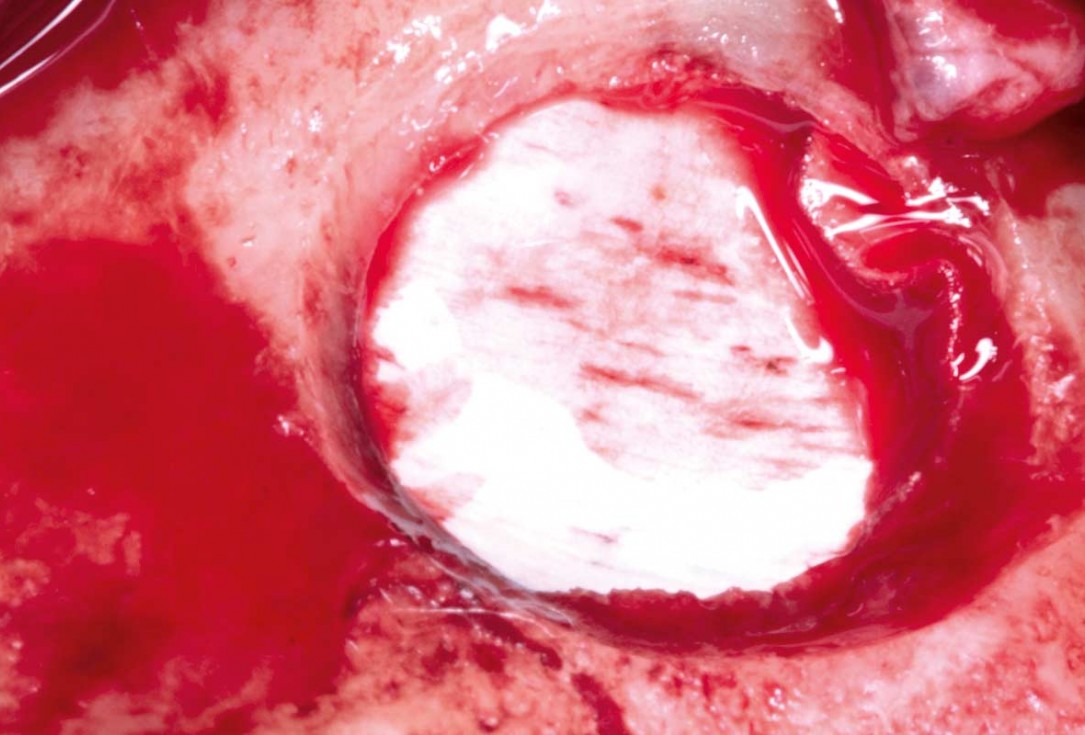

05/35 - Detached sinus membraneMaxillary sinus cyst removal using the Crocodile Technique and subsequent lateral sinus lift - Dres. C. Scognamiglio and A. Perucchi